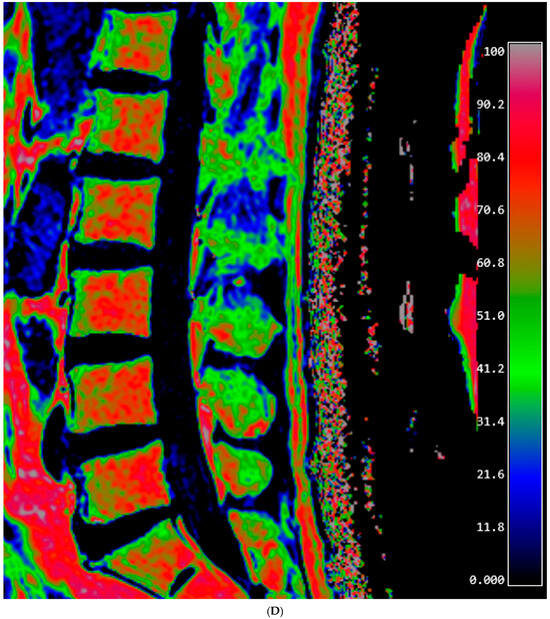

Figure 1.

Lumbar spine MRI of a 59-year-old male. (A) Fat fraction (FF) measurement on gradient-echo (GRE)-based chemical-shift-encoded magnetic resonance imaging (CSE-MRI). The FFGRE in this patient was 66.91%, representing the median value of the L1–L4 vertebral bodies. (B) FF measurement on spin-echo (SE)-based CSE-MRI. The FFSE was 85.84%. The numbers in the figure indicate the ROI numbering in the EXPRESS program. (C) Measurement of the vertebral bone quality (VBQ) score was calculated by dividing the median value of T1-weighted signal of L1–L4 vertebral bodies by the cerebrospinal fluid (CSF) signal at the L3 level. The VBQ score for this patient was 2.63. (D,E) FF color maps were created through GRE- and SE-based CSE-MRI.